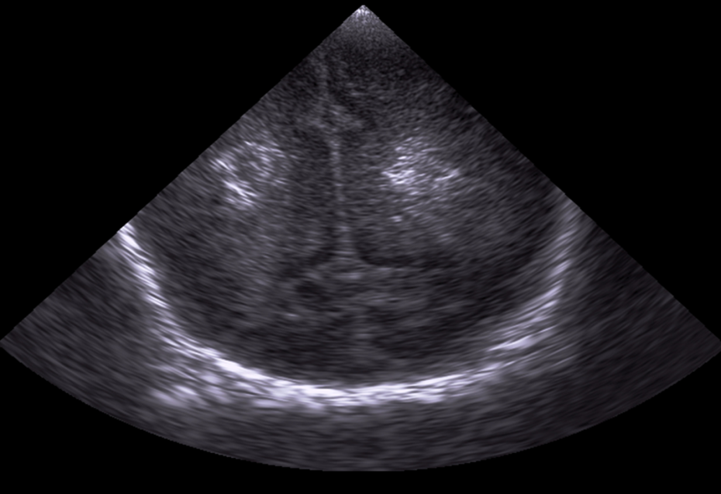

Neonatology Grade 1 PVL 4 Image